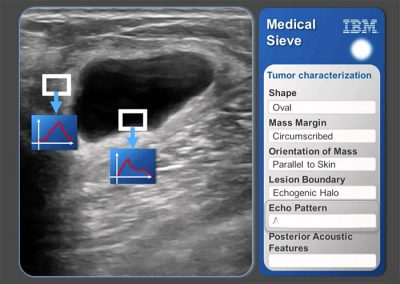

ஐ.பி.எம் நிறுவனத்தின் இன்னொரு மென்பொருள் மெடிக்கல் சீவ் (மருத்துவ சல்லடை). கதிரியிக்கவியலிலும், இருதயவியலிலும் படங்களை அலசி ஆய்வு செய்து பிரச்சனைக்குரிய பகுதிகளை மனிதர்களை விட கூடுதல் துல்லியத்துடன் அடையாளம் கண்டு நோயை கண்டுபிடித்து சொல்கிறது மெடிக்கல் சீவ்.